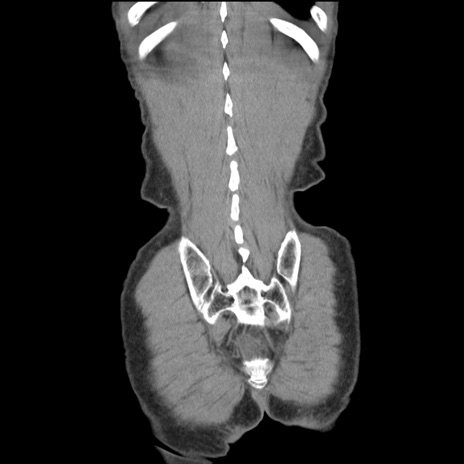

症例11(冠状断像)

【症例】 60歳代男性

【主訴】 下腹部痛

【現病歴】 本日夜中より下腹部痛の症状認め、受診。

【既往歴】 膀胱癌(膀胱全摘+尿管皮膚瘻術) 、胃癌術後

【身体所見】 BT 35.3℃、PR 58/min、BP 136/98mHg、腹部平坦、軟、腸蠕動音±、ストマ留置あり、左上腹部~正中部に圧痛あり、反跳痛なし。

【データ】WBC 5100、CRP0.01